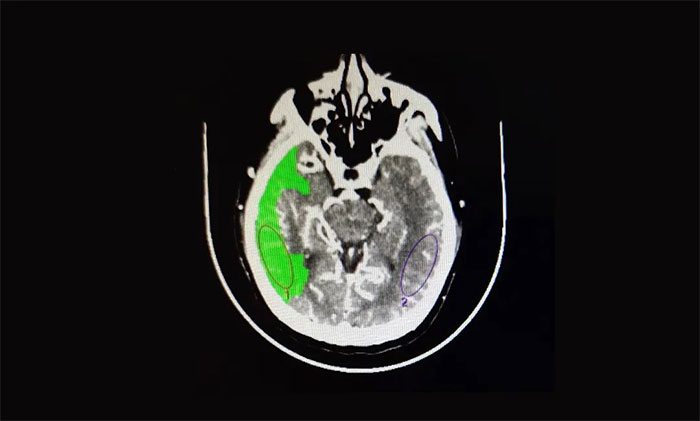

医院脑血管病病区主任张琪博士指出,患者从症状上看考虑急性大血管闭塞。急诊头颅CT平扫提示:右侧枕顶叶低密度灶;头颅CTA提示:右侧大脑中动脉M1段节段型重度狭窄;头颅CTP:右侧大脑半球脑组织灌注不足,存在缺血半暗带。

▲ CTA提示:右侧大脑中动脉M1段节段型重度狭窄

▲ 头颅CTP:右侧大脑半球脑组织灌注不足

综合患者病史和影像检查,诊断为:急性脑梗死(右侧大脑中动脉闭塞),如果不做手术,患者右侧大脑半球将大面积脑梗死,死亡率极高,病情十分凶险。在跟家属沟通并征得同意后,张琪博士决定为其实施血管内介入治疗。